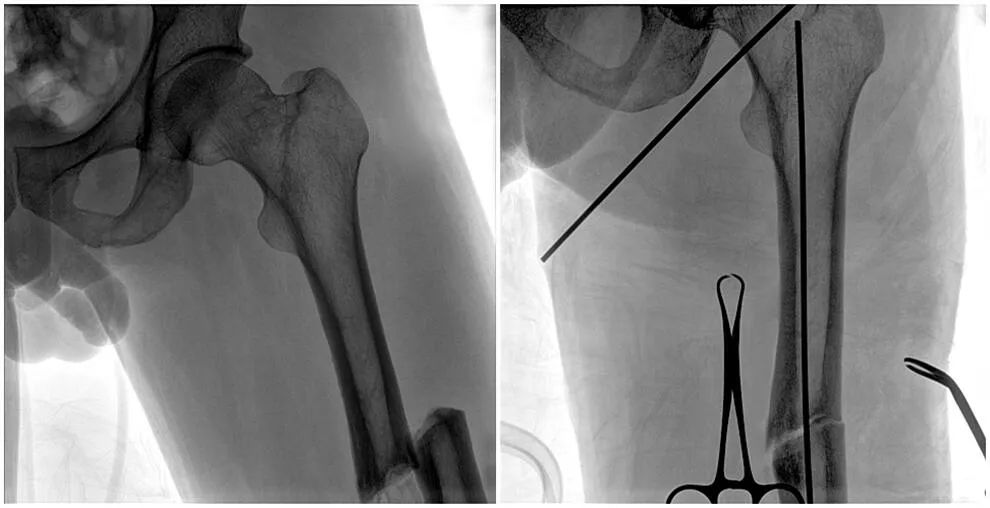

C形臂輔助手術過程

術中使用普愛醫(yī)療大平板一體式C形臂進行透視,判斷骨折情況及克氏針、髓內(nèi)釘?shù)冉饘僦踩胛锏奈恢茫M行調(diào)整。C形臂準確的術中定位,大大縮短了手術的時間,減輕了患者的痛苦,輔助手術順利完成。

在進行髓內(nèi)釘內(nèi)固定術時,醫(yī)生需要同時觀察到入釘點和骨折部位的情況,普愛醫(yī)療大平板一體式C形臂采用30CM×30CM的平板探測器,能夠呈現(xiàn)更廣闊的成像面積,滿足大部分長骨髓內(nèi)釘內(nèi)固定術的攝片需求。

術中定位準確、出血量少,術后影像顯示股骨移位糾正,恢復良好力線,手術效果良好。